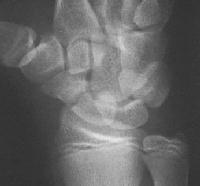

Clinical Example: Scaphoid fracture with total avascular necrosis similar to Preiser's disease

One of the problems with scaphoid fractures is ischemia of the proximal fracture fragment resulting in delayed union, nonunion or irretrievable avascular necrosis. In this case, ischemic changes involving the entire scaphoid are documented following a scaphoid fracture due to minimal trauma. This progressed with cystic changes and AVN on MRI. The patient had persistent pronounced wrist stiffness and pain. As pointed out to me by Dr. Lawrence Schneider (thanks!), this is technically not true Preiser's, for the fracture preceded the AVN.